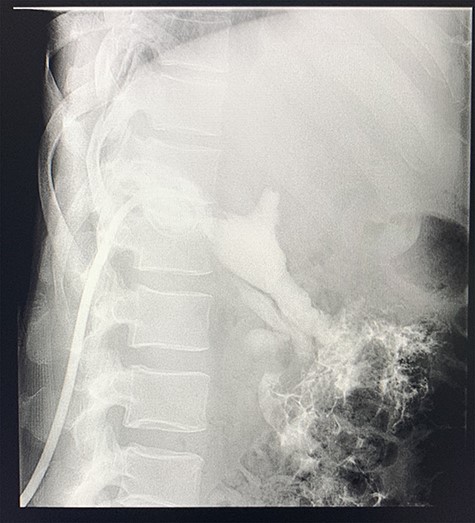

A size 12 French percutaneous catheter was inserted into the large liver abscess. The purulent material drained tested negative for organisms, amoebic and hydatid disease (Fig. 4). A sinogram was performed by injecting contrast through the catheter, showing passage into the ascending colon, confirming the initial diagnosis (Fig. 5).

Sinogram obtained by anterioposterior x-ray of segment of lower chest/abdomen following injection of contrast into the percutaneous pigtail catheter, demonstrating passage of contrast into the hepatic flexure of the colon via an apparent fistulous connection.